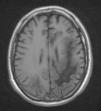

Se efectuó resonancia magnética por imágenes (RMI) con contraste en la que se observó extensa lesión subcortical en lóbulo frontal, parietal y occipital izquierdos, con extensión al esplenio del cuerpo calloso y mesencéfalo superior del lado izquierdo, y compromiso de los lóbulos parietal y occipital derechos. Las imágenes predominaban en lóbulos posteriores y dibujaban las fibras subcorticales en «U». No hubo realce con el contraste IV, ni efecto de masa sobre estructuras adyacentes de la línea media (figs. 1-5).

El VJC se reactiva ante cuadros de inmunosupresión grave, e induce la infección lítica de los oligodendrocitos con lesiones multifocales de desmielinización. La enfermedad tiene una prevalencia del 1 al 4% entre los pacientes con sida. El curso clínico es progresivo y con déficit neurológico focal en el 80% de los pacientes afectados. El examen del LCR es normal o con alteraciones inespecíficas, (hiperproteinorraquia moderada y pleocitorraquia mononuclear)4. La RM muestra la presencia de lesiones, por lo general bilaterales, simétricas o asimétricas, con predominio en lóbulos parieto-occipitales, bien delimitadas y localizadas en áreas periventriculares y en la sustancia blanca subcortical. Pueden ser únicas o múltiples, no refuerzan con el contraste, no están rodeadas de edema, ni producen efecto de masa, y dibujan las fibras subcorticales en «U» o fibras arcuatas; un tercio de los pacientes tienen compromiso de la fosa posterior. Entre un 5-10% de los casos, esta última localización se revela como la única manifestación de la enfermedad4. El diagnóstico se confirma por la PCR en el LCR. La sensibilidad de la prueba es variable (40-80%), posee una alta especificidad (mayor del 90%) y un valor predictivo positivo del 100%5.